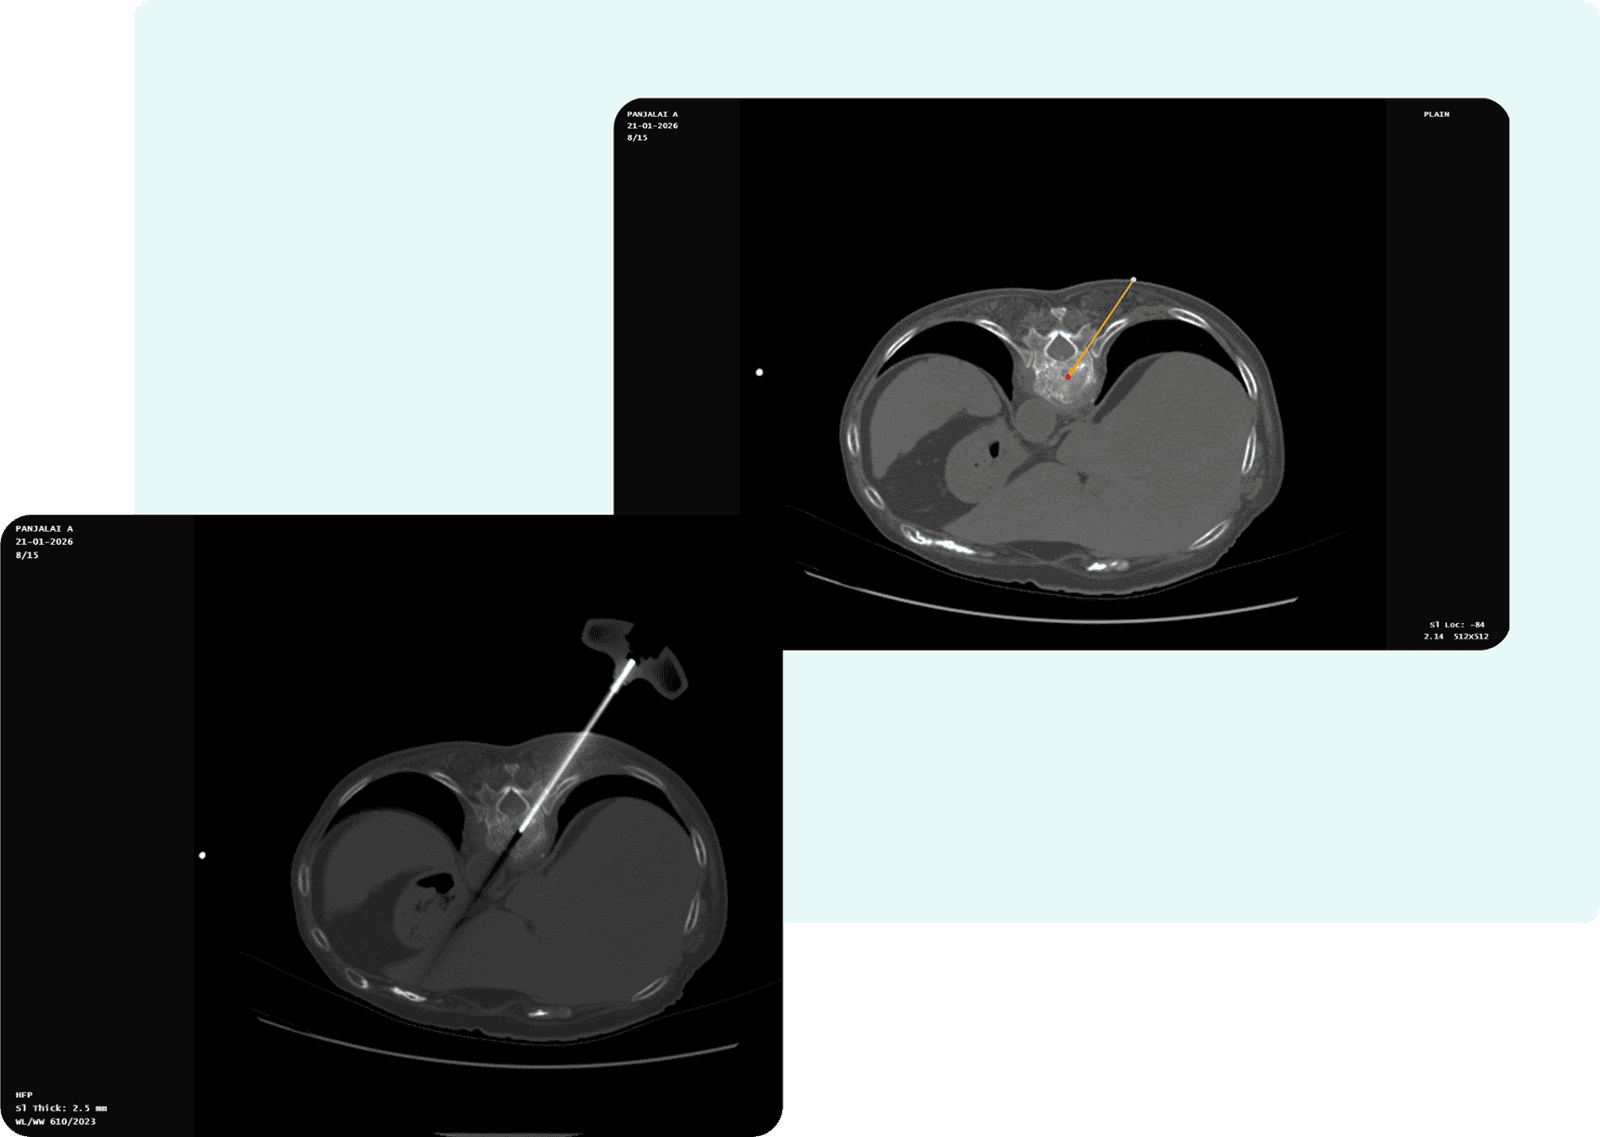

- Needle Length: 2.03cm

- Entry Slice Number: 8

- Target Slice Number: 10

- Orbital Angle: 42.27°

- Cranio-Caudal (CC) Angle: -18.93°